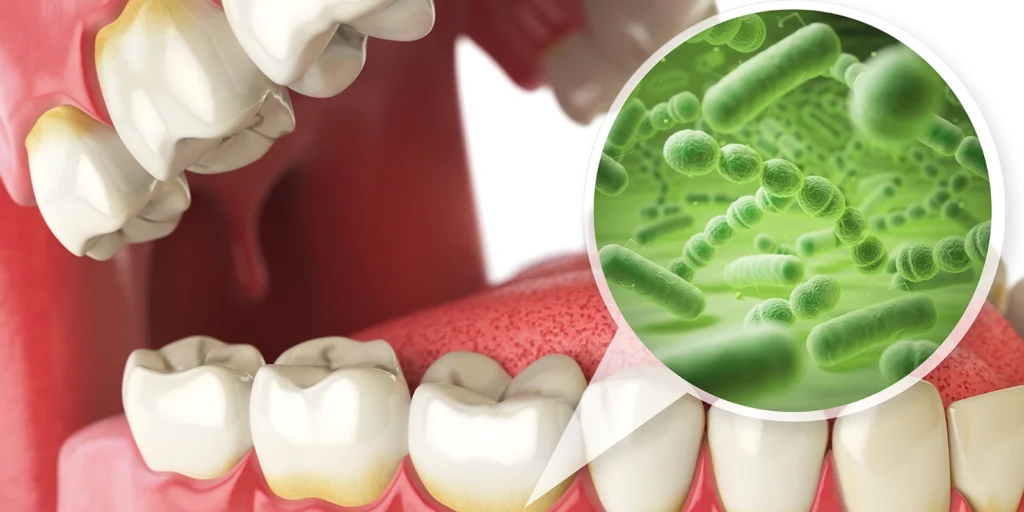

口臭の悪化、歯周ポケット内の細菌が産生する揮発性硫黄化合物

歯周病が進行すると、歯周ポケットの中で嫌気性細菌(酸素を嫌う細菌)が増殖し、「揮発性硫黄化合物(VSC)」と呼ばれるガスを産生します。このガスが口臭の原因となります。

具体的には、硫化水素(卵が腐ったようなにおい)やメチルメルカプタン(腐った野菜のようなにおい)が主成分です。

歯周病による口臭は、歯磨きやマウスウォッシュでは一時的にしか改善しません。口臭の原因が歯周ポケット内の細菌にあるため、歯周治療によってポケット内の環境を改善しない限り根本的な解決にはならないのです。